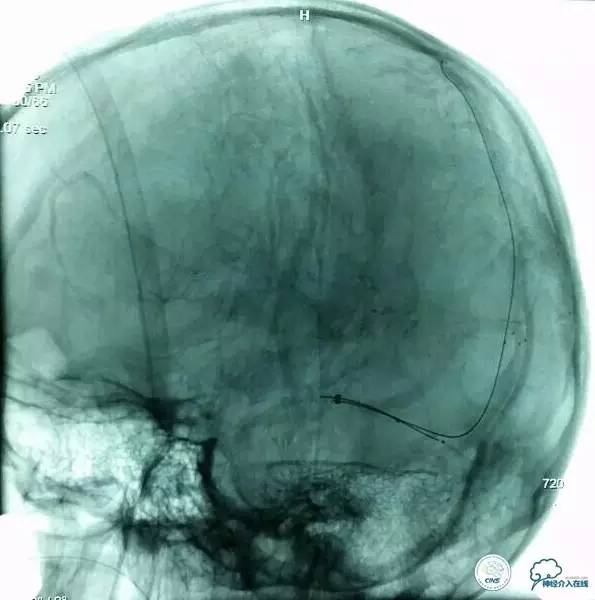

▼导丝,支架位置:

▼支架释放:

▼确定微管位置:

▼第三次取栓后造影,窦通畅,下矢状窦显影延迟,说明上矢状窦通畅了。

▼正位: